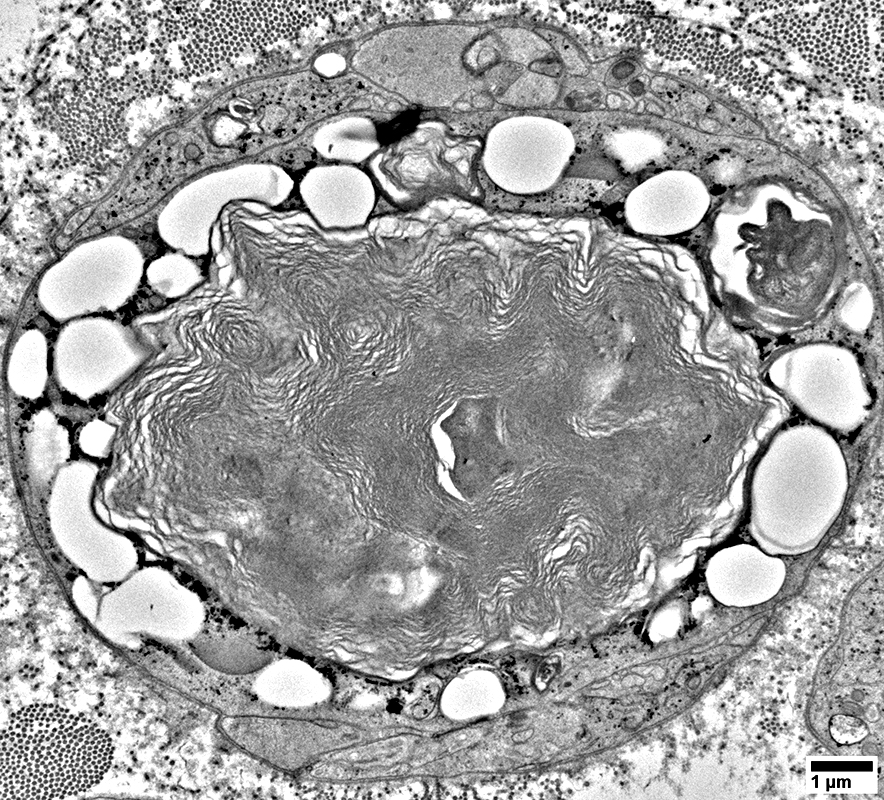

Schwann Cells

Some contain Lipid debris

Myelin Damage: Lipid Droplets & Ovoids in Schwann cells

Myelin Damage: Lipid Droplets & Myelin debris in Schwann cells

Myelin Damage: Lipid Droplets & some Myelin debris in Schwann cells